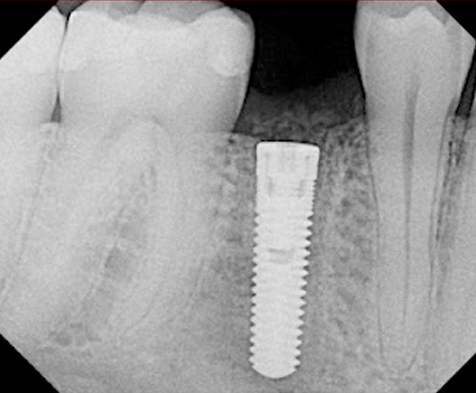

• اول به اين معني است که دندانپزشک قطعه اول ايمپلنت يعني فيکسچر را در داخل استخوان فک بيمار قرار داده و هنوز جاي دندان طبيعي خالي مي باشد. در اين حالت بيمار بايد دو الي سه ماه صبر کند تا فيکسچر با استخوان فک پيوند برقرار کند و سپس مراحل بعدي انجام شود.

• دوم يعني دندانپزشک فيکسچر را در استخوان فک قرار داده است و بعد از گذشت دو الي سه ماه، قطعه دوم ايمپلنت را که هيلينگ نام دارد روي فيکسچر بسته تا در اطراف آن لثه شکل بگيرد. سپس قطعه سوم (اباتمنت) به همراه دندان چيني (ساخته شده توسط دندان ساز) که تکميل کننده ايمپلنت مي باشد، به جاي هيلينگ قرار مي گيرد. دندانپزشک دندان چيني را روي اباتمنت مي چسباند. در اين زمان بيمار مي تواند همانند دندان طبيعي از دندان مصنوعي خود استفاده کند.